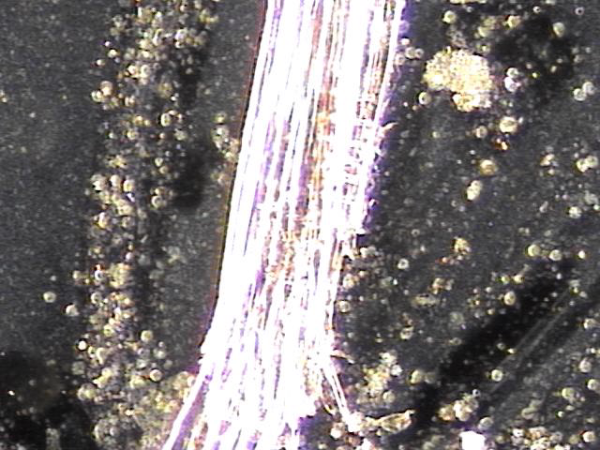

전립선과 사정관입구와 사정관 그리고 정낭과 정관의 표적 치료후 사정관 입구의 결석들이 치료된 현미경학적 자료 입니다.

This microscopic image was taken after targeted treatment of the prostate, the entrance of the ejaculatory ducts, the ejaculatory ducts themselves, the seminal vesicles, and the vas deferens.

The specimen shown here appears to be a calcified deposit or stone-like material (ejaculatory duct calculi). Such structures can form when shed epithelial cells, inflammatory debris, or proteinaceous substances accumulate and harden over time, often as a result of chronic inflammation or impaired circulation in the ducts.

For a more precise interpretation, consultation with international experts in urology, pathology, and andrology would be valuable, as their collective opinions could help confirm whether this represents a true ejaculatory duct stone, calcified tissue, or another type of mineralized deposit.

In practical terms for patients, this image suggests that treatment has helped dislodge and clear these obstructive materials, which is a positive sign for improving ductal flow and overall reproductive health.